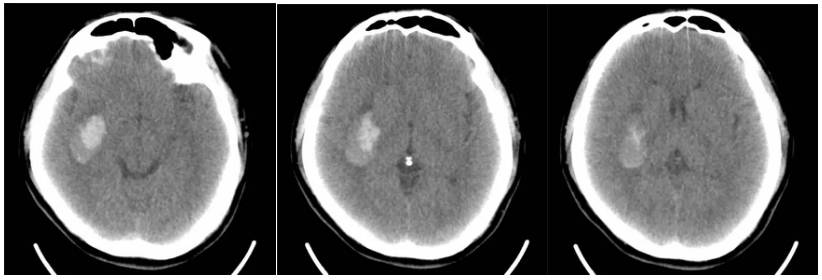

救护车载移动CT陈旧性脑梗塞扫描

救护车载移动CT扫描脑出血后软化灶形成